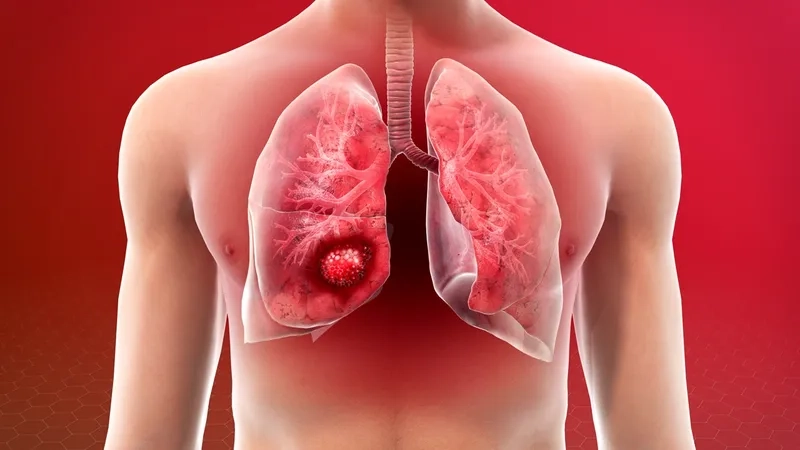

Tumor progression in small cell lung cancer